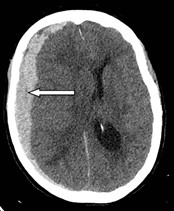

Analice bien la imagen de un paciente adulto mayor (de 84 años) con pérdida de memoria y marcha tres meses posteriores a una caída. Por correlación neuroanatómica esta hemorragia es de tipo

100%